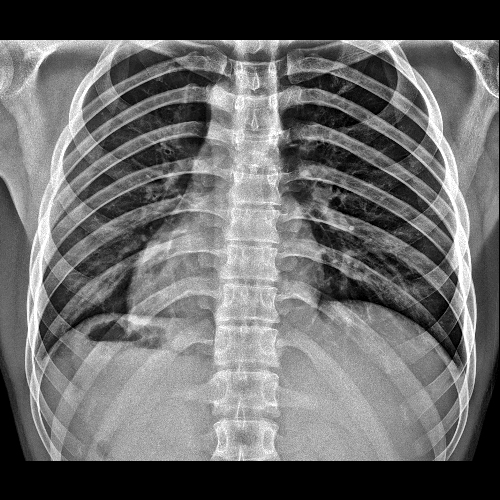

1. 图像过亮:

使得图像中的组织结构细节显示不清,对比度降低。例如,在胸部 X 线成像中,过大的曝光量可能会导致肺部纹理、肋骨等结构变得模糊。

2. 灰雾度增加:

图像整体显得灰暗,降低了图像的清晰度和质量。比如在骨骼 X 线成像中,灰雾度过高会使骨小梁等细微结构难以分辨。